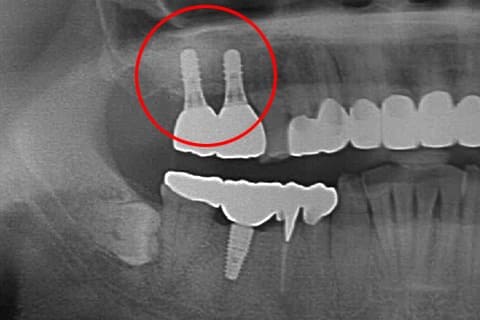

CASE.02 「GBR・骨誘導再生法」

-

- 治療内容

- GBR・骨誘導再生法

- 治療費用

- ¥110,000